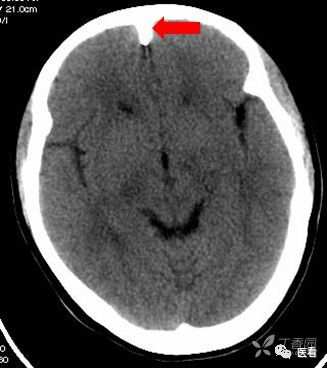

颅底(致密)骨产生的横行或放射状伪影,与设备性能也有关系

下图为16拍MSCT,伪影较轻。

此图为双排螺旋 CT图像, 伪影较16层及以上MSCT显著的多。